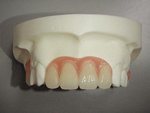

◆総入れ歯

当院の総入れ歯では、リンガライズド・オクルージョンという特別な噛み合わせで製作しております。この噛み合わせの特徴は、小さな力で食品を破砕することが可能となり、顎堤が吸収して食事中、入れ歯の安定が悪い方にお勧めです。

総入れ歯1

総入れ歯2

総入れ歯3